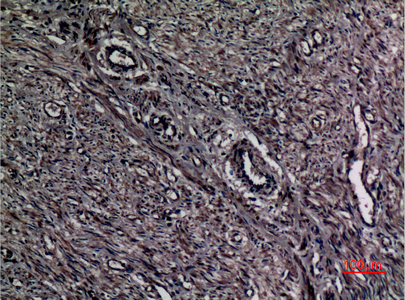

Immunohistochemistry analysis of paraffin-embedded Human uterus using A1BG antibody.High-pressure and temperature Sodium Citrate pH 6.0 was used for antigen retrieval.